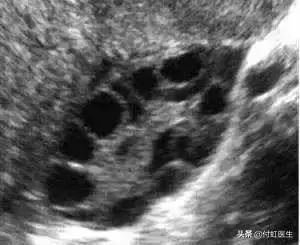

3. B超:临床医生可以通过超声检测卵巢体积、基础窦卵泡数目(AFC)、卵巢动脉血流来评估卵巢储备功能,其中基础状态(月经第2~3天)的卵巢体积变小与卵巢储备的原始卵泡减少、卵泡生长的数目少有关。

窦卵泡数AFC减少,窦卵泡指早卵泡期直径2~9mm的卵泡,通常认为双侧卵巢窦卵泡数合计少于5~7个提示卵巢储备功能下降。

做B超检查我们看到,涓涓的窦卵泡数AFC,左侧卵巢4-6mm的卵泡10个,右侧卵巢4-6mm的卵泡8个,属于正常状态。